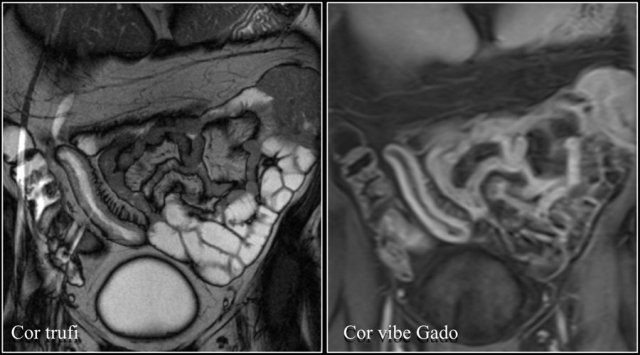

Here we see a coronal T2W-image and a coronal T1W-image with fatsat.

Notice that the small bowel is well distended.

Luminal distension should be ≥ 2 cm.

Bowel wall thickness > 3 mm is considered abnormal.

Collapsed small bowel loops can be easily misinterpreted as wall thickening or abnormal enhancement.

On the coronal T1W-image the jejunal loops are collapsed.

As a result it looks as if there is bowel wall thickening and prominant enhancement.

On the T2W-image during the same examination there is normal distention.